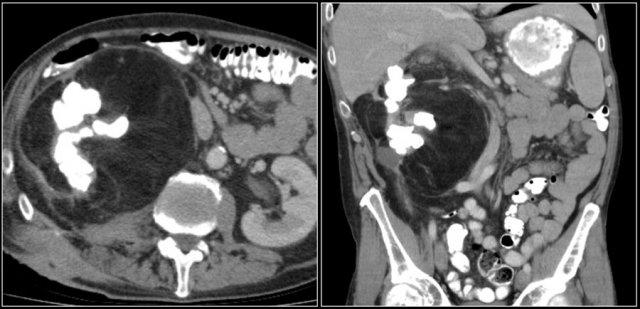

Tổn thương xâm lấn ở cực dưới thận phải, phát triển đáng kể sau sáu tháng, kèm theo hạch bạch huyết lan rộng. Đây được xác định là di căn của ung thư phổi.

Các khối u ác tính nguyên phát thường di căn đến thận nhất bao gồm ung thư phổi, ung thư vú, các khối u đường tiêu hóa và u hắc tố (melanoma).

Di căn thận thường xuất hiện muộn trong tiến trình của một bệnh ác tính đã biết, như một phần của bệnh lan rộng toàn thân.

Trong một số ít trường hợp, di căn thận có thể biểu hiện dưới dạng một tổn thương đơn độc và khó phân biệt với ung thư biểu mô tế bào thận.

Di căn thận thường có kích thước nhỏ, đa ổ và hai bên, với hình thái phát triển xâm lấn.

Các tổn thương này ngấm thuốc nhẹ, kém hơn nhiều so với nhu mô thận bình thường.

Hình ảnh cho thấy bệnh nhân có nhiều tổn thương di căn thận.

Lưu ý huyết khối khối u trong tĩnh mạch thận trái.

Đây là hình ảnh của một bệnh nhân ung thư phổi.

Có một tổn thương di căn ở thận trái và nhiều tổn thương di căn hạch bạch huyết (mũi tên).

Nếu đây là biểu hiện duy nhất, sẽ rất khó để phân biệt với ung thư biểu mô tế bào thận có di căn hạch bạch huyết.